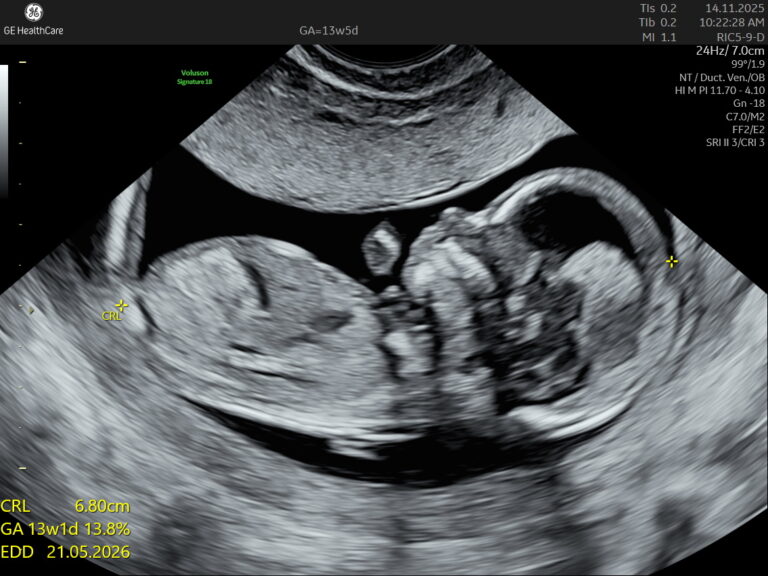

The first trimester — the first 13 weeks of pregnancy — is perhaps the most transformative period in...

Got you — here’s a clean, authoritative yet super-readable pillar page on First Trimester Screening,...

Fetal Well-being Scan Red Flags: What Parents Need to Know in Kolkata